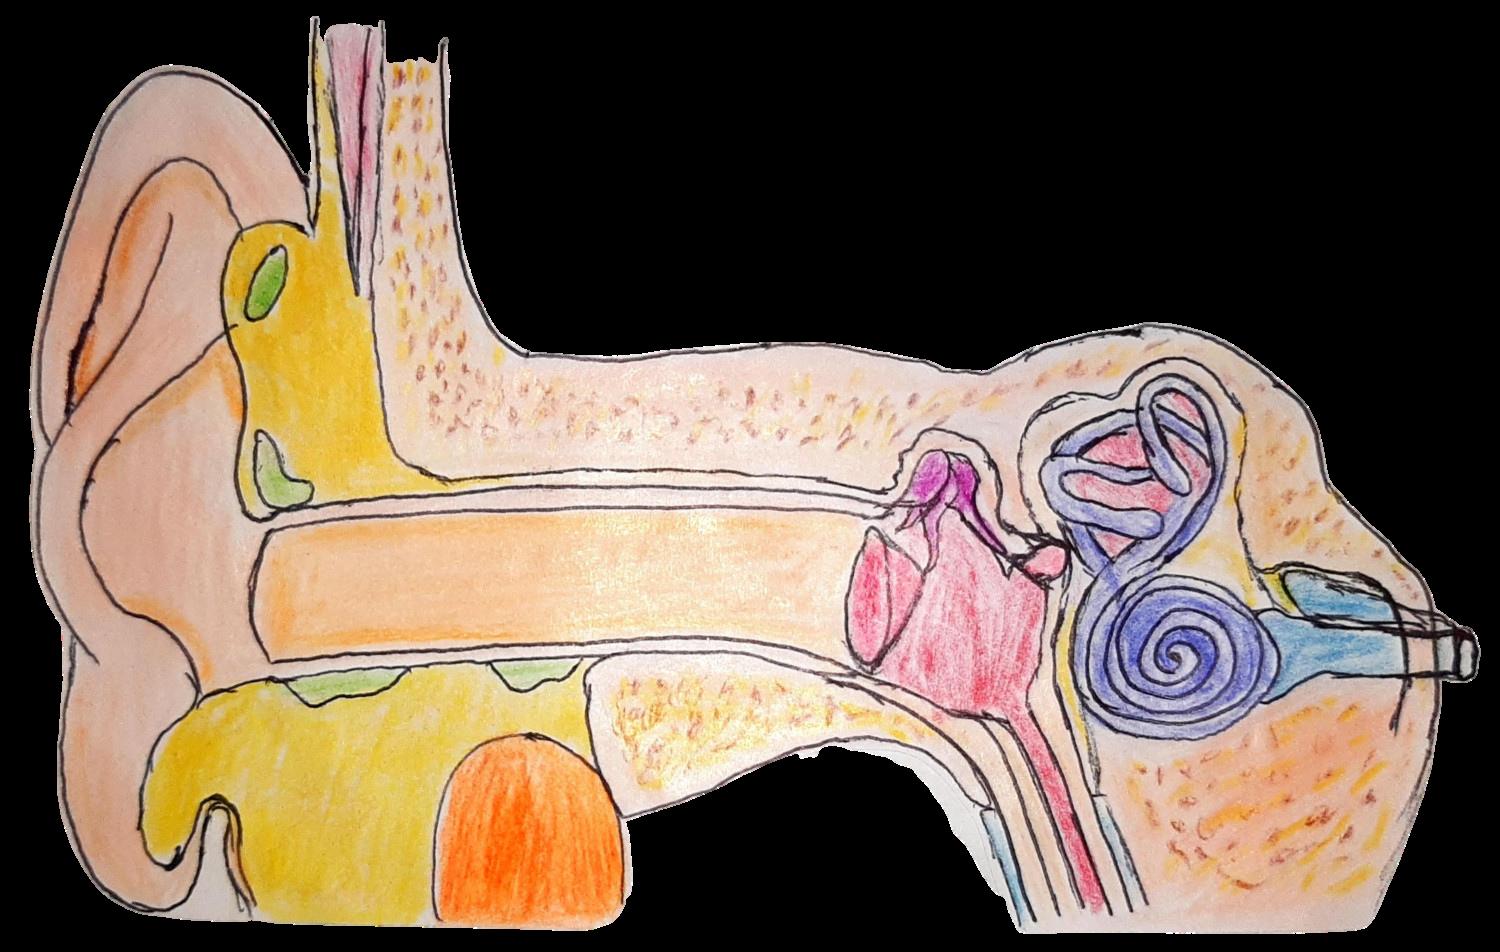

CARACTERÍSTICAS:

Lleva los impulsos para la coordinación del equilibrio Transmite la información sobre la posición espacial de nuestra cabeza y cuerpo y, el automovimiento

Nervio auditivo Nervio

Trompa de

Yunque Martillo Membrana timpánica Canal auditivo externo Rama

Rama

Cigomática

Bucal Rama Mandibular

NERVIO VESTIBULAR

facial Cóclea Canales semicirculares Estribo

Eustaquio

Cervical

NERVIO VESTIBULAR (VIII

FACIAL (VII PAR)